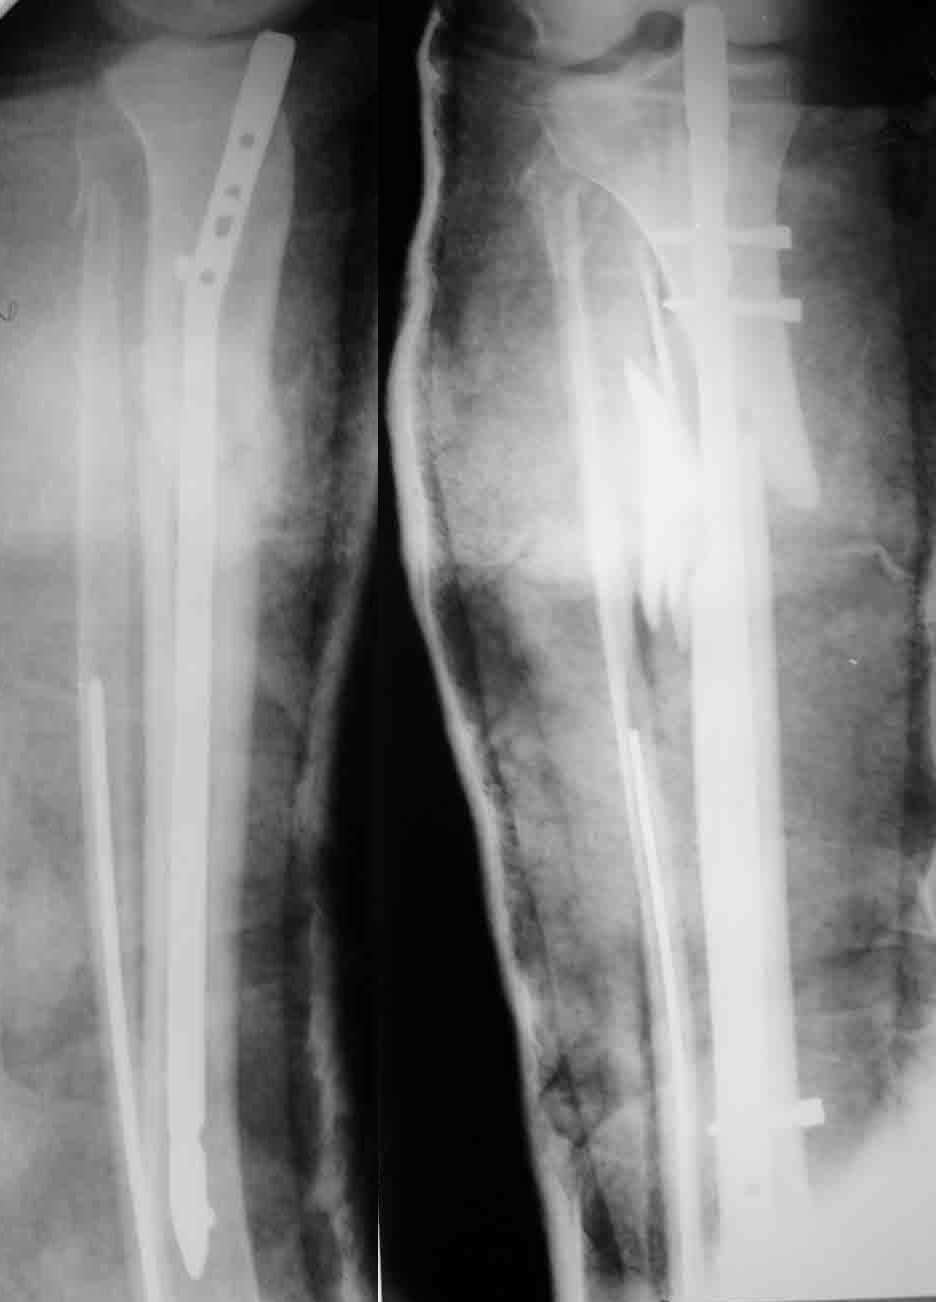

Молодой женщине по поводу бамперного перелома через 2 недели после травмы выполнен остеосинтез большеберцовой кости гвоздем ChM в одной из больниц Москвы. Снимок приложен. Сейчас речь пошла об удалении гвоздя и остеосинтезе пластиной. Действительно ли это оптимальный план? Какие есть еще варианты?

A female 24 years old, a sister of a friend of mine (not physician) living in Moscow, 3 weeks ago admitted to the hospital in Moscow after a car accident (was a pedestrian) with a tibial shaft fracture. 3 days ago closed locked nailing was performed, see attached films. Now he is in panic because they are going to remove the nail and perform plating.

It seems to me the situation can be solved on the current nail with a minimal procedure - insertion of wires into distal and proximal tibia, acute distraction and proximal static locking. Maybe dynamic locking screw should also be removed before. As a maximum i would assume to pull the nail to the central fragment, insert poller wire or screw, then insert of the nail back and lock it.